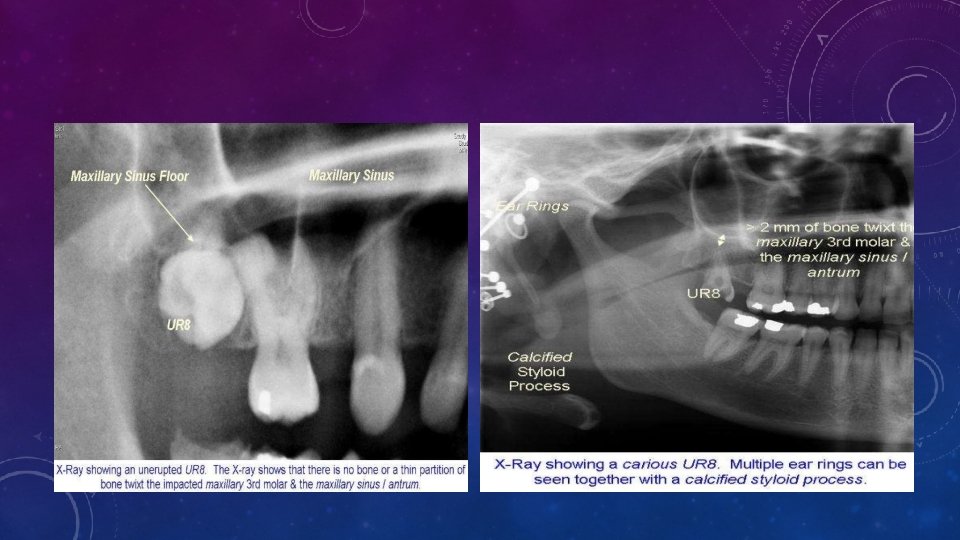

4. Based On Relationship Of Impacted Max 3 rd Molar To The Max Sinus • Sinus Approximation (S. A) no bone or a thin partition of bone between the impacted tooth and the maxillary sinus. • No Sinus Approximation (N. S. A) 2 mm or more bone present 5. Based on nature of roots • Fused • Multiple

DEGREE OF DIFFICULTY • Angulation - opposite to mandibular 3 rdmolar. • Distoangular < Vertical< Mesioangular impaction • In MA impactions, bone in distal region is more and dense with less accessability. • Buccoangular position: more buccal more easy, less bone removal needed. • Type of overlying tissue - Easier if soft tissue covering only. • Sinus poximity – Chance of oro antral communiation. • Poximity to tuberosity – chance of fracture.